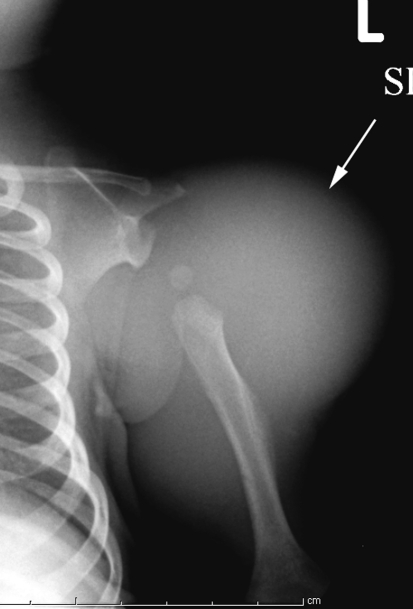

Fig. 3.

An AP radiograph of the right shoulder shows a large soft tissue mass in the lateral aspect of the upper arm. There is periosteal bone reaction to the mass, with remodeling and new bone formation appearing as a result of a pressure phenomenon from the tumor against the bone.

Plain radiographs (Fig. 3) showed a large soft tissue mass causing secondary humerus remodeling and slight valgus angulation but with no definitive bone invasion or scalloping. MRI showed this large lesion (Fig. 4) better. It was a well-circumscribed, discrete, heterogeneous mass, relatively isointense to muscle on T1-weighted imaging, with variable areas of moderately increased signal on T2-weighted images. In the areas of solid tumor, cystic fluid-fluid levels and tubular structures with varying signal intensity also were evident. The mass extended medially into the axilla and from the superolateral aspect of the arm to the distal third of the triceps compartment. There was no direct invasion of the bone or periosteum.